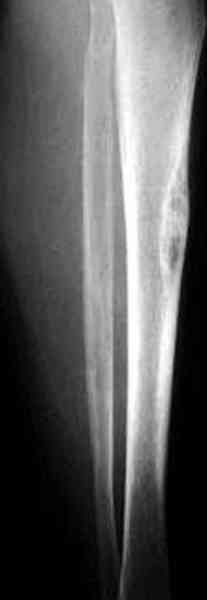

"При его рассмотрении с рентгенологом и морфологом сошлись, что это не фиброзная дисплазия, что было первым предположением по рентгенограммам. В полости было и мягкотканое образование. Окончательно заключение дадут через несколько дней"

По локализации и по характреру опухоли мало напоминает остеобластому, может, представленные биопсийные материалы адамантиномы помогут вашим морфологам дифференцировать опухоль (Basiloid cells, pseudoglandular pattern and peripheral palisading)

Недавно на нашей ежемесячной Morbidity&Mortality

conference мы разбирали похожий случай, ложный сустав большеберцовой кости после резекции опухоли.

К нашему онкологу-ортопеду обратился больной с жалобами на боли в голени, из рассказа - год назад была сделана биопсия большеберцовой кости, но название заболевания "не запомнил”.

Оперирован в военном госпитале с заменой сегмента

аллокостью большеберцовой кости и после демобилизации явился для постоянного наблюдения по месту жительства.

В литературе "A Classic Adamantinoma Arising from

Osteofibrous Displasialike Adamantinoma in the Lower Leg: A case report and Review of the Literature похожие снимки.

Наши имели проблему со сращением, пришлось им сделать динамизацию, дополнительную аутопластику.

Снимки представлены.